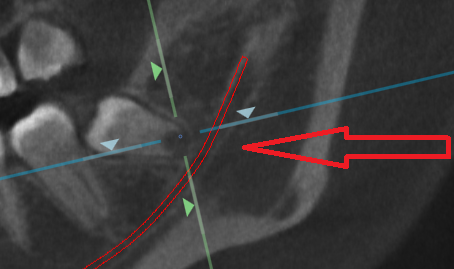

精査のためにCTレントゲン写真を撮影しました。 左下の親知らずは、ほとんどが骨に埋まっています。

更に詳細を分析します。

赤いチューブのような線は、下顎管といわれる動脈と神経で、親知らずの根の先と、かなり距離が近いです。